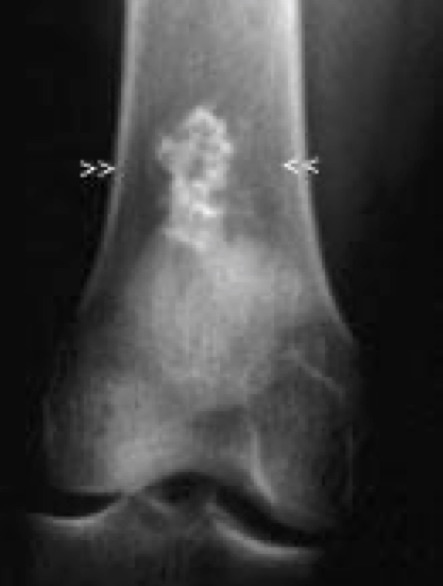

Chondroid

Usually easier to recognize cartilage vs osteoid by the presence of focal stippled or flocculent densities, or in lobulated areas, as rings or arcs of calcifications.